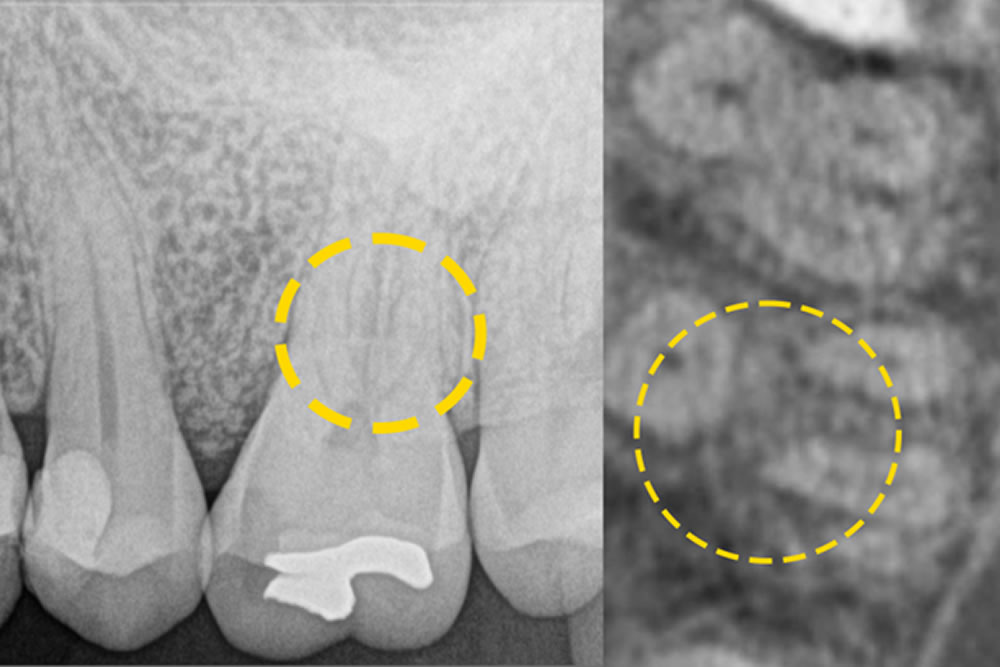

こちらの患者さまは、左上の第一大臼歯の近心部に「垂直性骨欠損」が認められ、歯周病の進行により歯を支える骨が深く失われていました。また、同じ歯の根の分かれ目(分岐部)にも炎症が広がっており、「根分岐部病変」という状態でした。これは、歯の根が分かれている部分まで歯周病が進行し、プローブが分岐部の中ほどまで届くような中等度の病変を意味します。

このような症例では、通常のクリーニングや歯周ポケットの治療だけでは改善が難しいため、当院では最小侵襲手術(MIST)を行いました。マイクロスコープ(顕微鏡)を使用して分岐部の状態をしっかり確認し、Er:YAGレーザーを用いて感染した組織を丁寧に除去。さらに、骨の再生を促す処置(再生療法)も併せて行いました。

治療後は定期的なメインテナンスを継続しており、現在も歯と歯ぐきの状態は良好に維持されています。